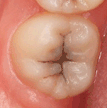

2. CÓDIGO 5

1. Cavidad visiblemente detectable con paredes en esmalte y piso en dentina.

1. DIAGNOSTICO DENTAL: CARIES CAVITACIONAL (ACTIVA / NO ACTIVA). Es activa cuando a la exploración clínica con cucharilla el tejido cariado se puede retirar acompañada de otros signos como encía enrojecida y presencia de sangrado, cuando es inactiva vemos que hay dentina reparativa de por medio, esta se ve opaca y no brillante.

1. TRATAMIENTO: Orientación en normas y educación de higiene oral al padre/madre/menor, control de placa, profilaxis, si esta lesión llega a afectar algún cuerno pulpar se debe de realizar una pulpotomía junto con una restauración ya sea en amalgama o composite, si esta lesión no es tan severa se retira la caries posterior a esto se realiza la reconstrucción de la pieza dental. Aplicación de barniz fluorado.